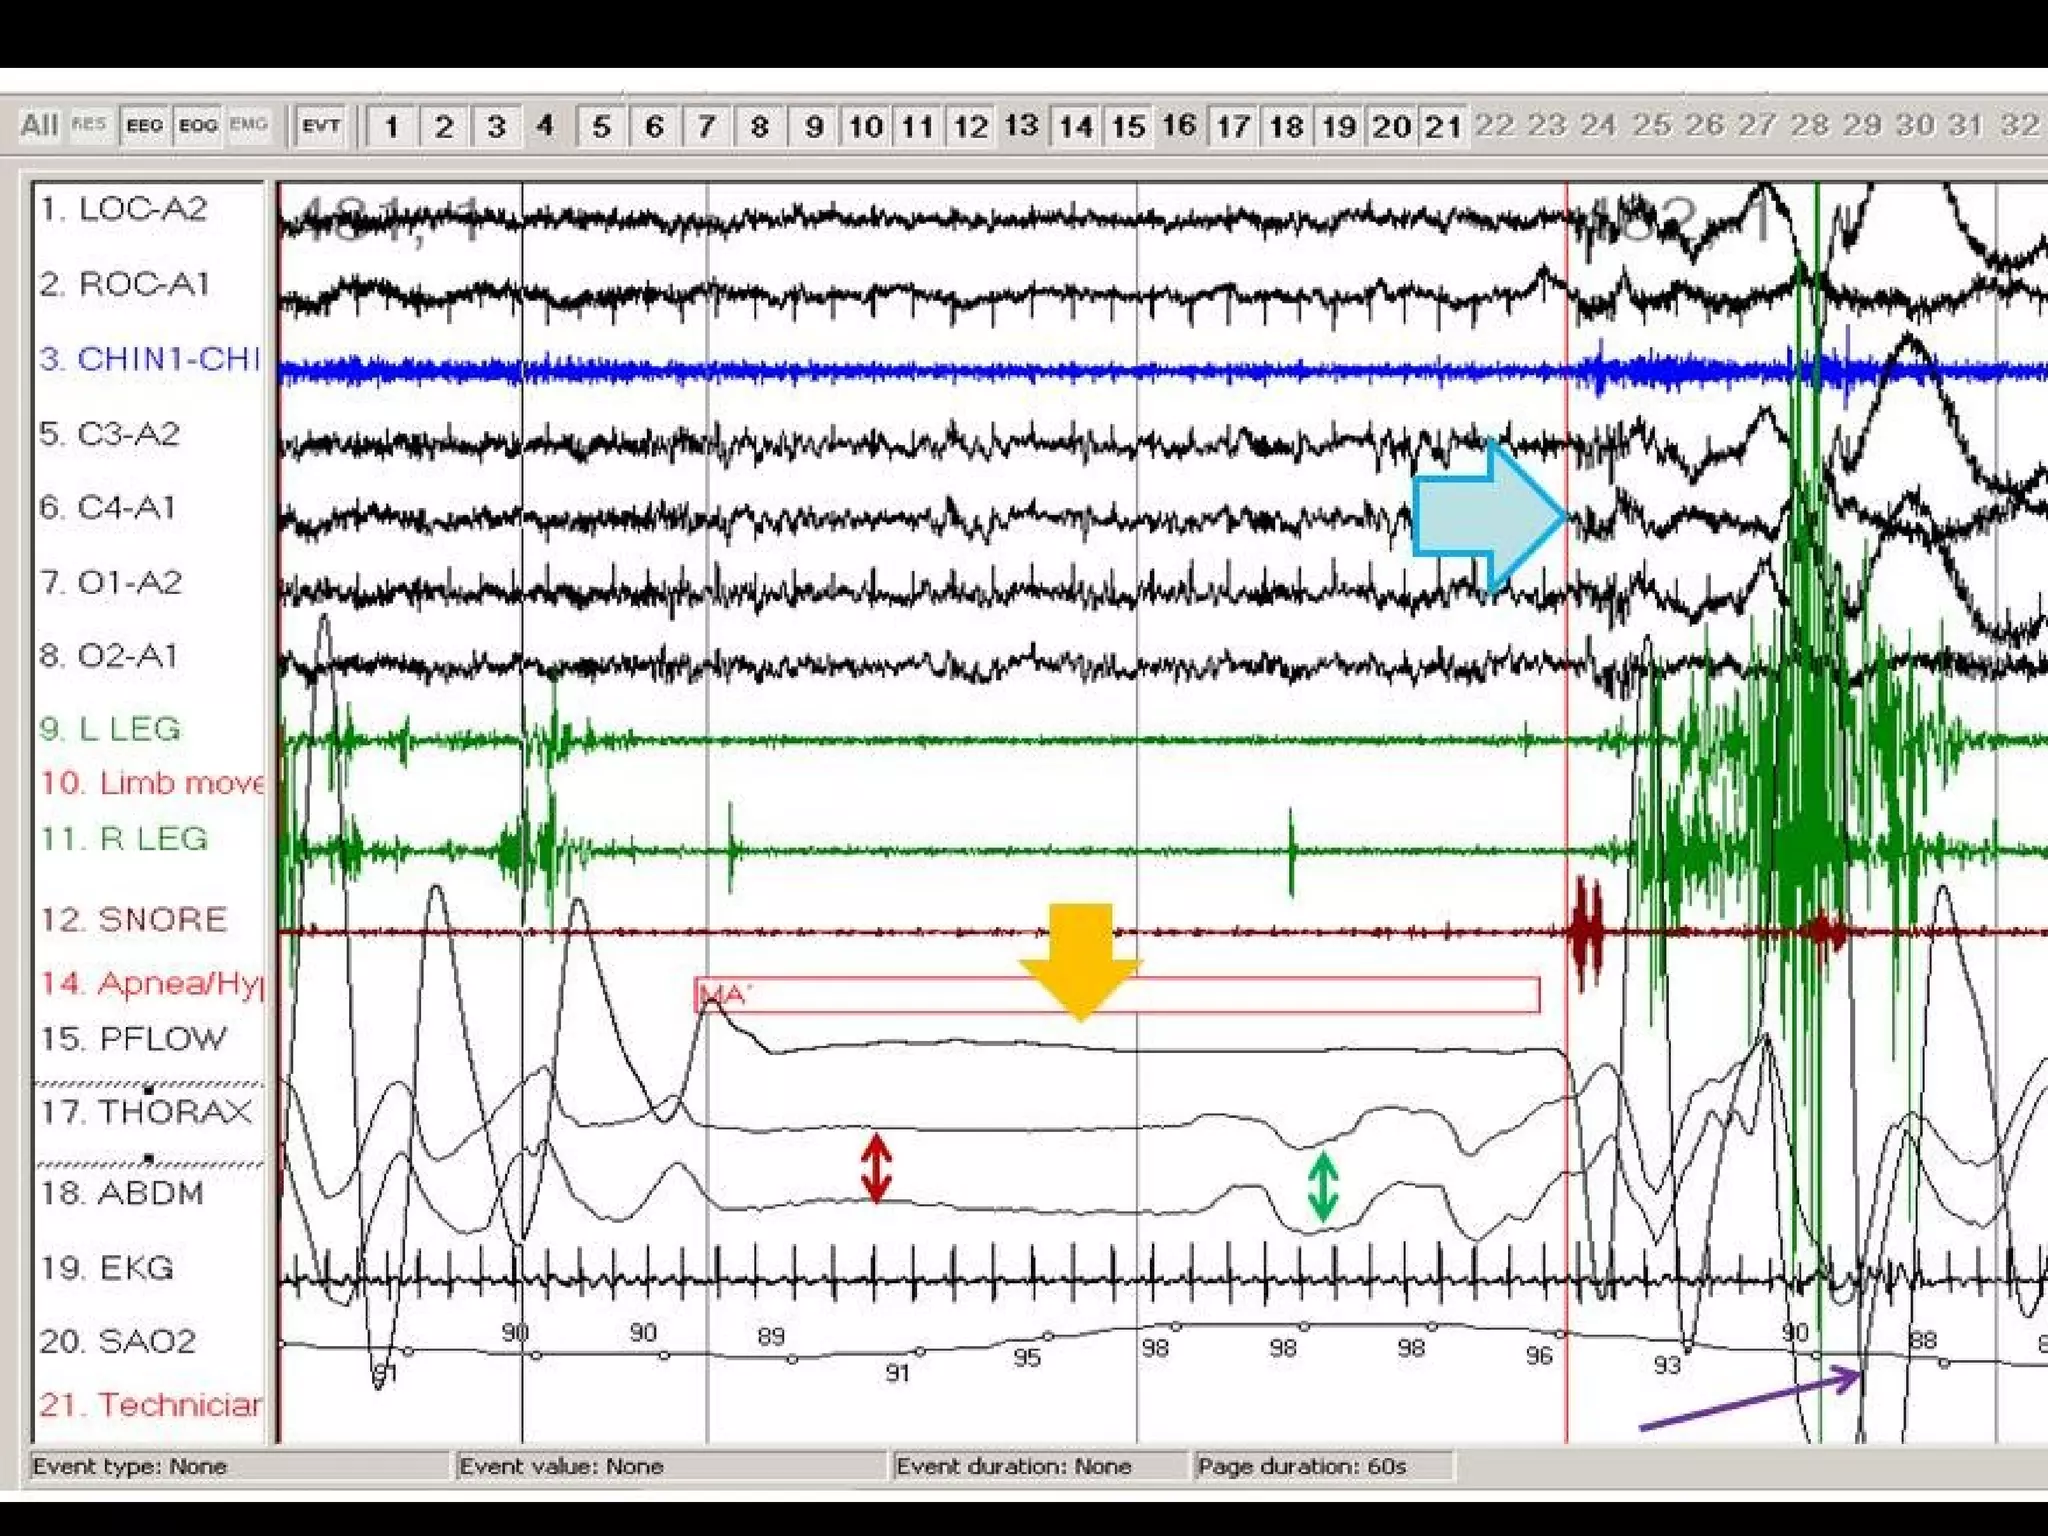

#43 Obstructive sleep apnea. Note the absence of flow (red arrow) despite paradoxical respiratory effort (green arrow).

#44 Comparison of a central apnea (box) and obstructive apnea (circle).

#45 Central sleep apnea (thick areas). Note the absence of both flow and respiratory effort (green double arrows).

Central apnea is the cessation of airflow for at least 10 seconds with no respiratory effort

#46 Mixed sleep apnea. Note that the apnea (orange arrow) begins as a central apnea (effort absent; red double arrow) and ends as an obstructive apnea (effort present; green double arrow). Note the arousal (blue arrow) that terminates the apnea and the desaturation (purple arrow) that follows

#48 Peroidic breathing at sleep wake transition.- Alternating hyperventilation and hypoventilation with apnea at nadir